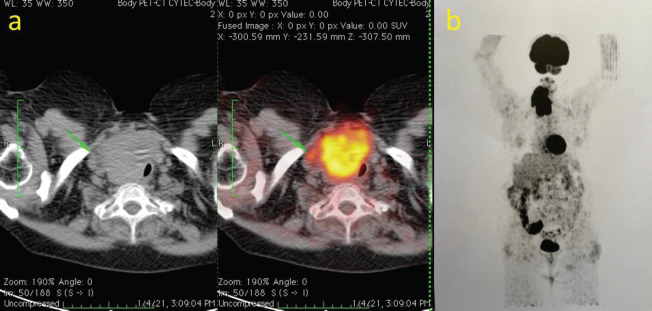

Case report: A 69-year-old female patient presented with a large mass in the right thyroid lobe measuring 10 × 8 cm. A computed tomography scan showed a mass with no cleavage plane between the tumour and both the laryngotracheal and esophageal right lateral wall. A core needle biopsy was performed and confirmed PDTC. The case was considered unresectable. After a trial of neoadjuvant lenvatinib was administered, a partial response of 50% was achieved and surgery could be performed with favourable surgical outcomes. The patient did not resume lenvatinib after surgery, as no evidence of structural disease was found. At publication, she remains free of structural disease with an incomplete biochemical response.